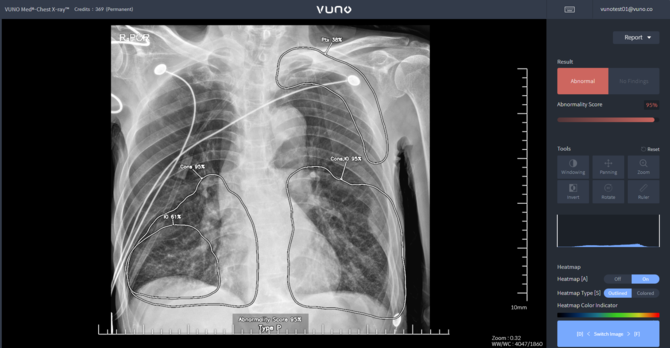

[프라임경제] 인공지능(AI) 기업 뷰노(338220)는 AI 기반 흉부 엑스레이(X-ray) 판독 및 소견 검출 의료기기 '뷰노 메드 체스트 엑스레이(VUNO Med®-Chest X-ray™, 이하 체스트 엑스레이)가 지난 1월 혁신의료기기 통합심사·평가에서 승인을 받은데 이어, 이달 보건복지부의 혁신의료기술 관련 고시가 확정됨에 따라오는 6월1일부터 비급여 시장 진입이 가능해졌다고 15일 밝혔다.

뷰노의 '체스트 엑스레이'는 안전성과 진료 현장에서의 잠재적 유용성을 인정받은 의료 AI 솔루션으로, 이번 고시에 따라 2025년 6월 1일부터 2028년 5월 31일까지 3년간 임상 현장에서 사용이 가능해졌다.

해당 제품은 흉부 엑스레이 영상을 분석해 △결절 △경화 △간질성 음영 △흉막 삼출 △기흉 등 5개의 이상 소견 유무를 검출하고, 소견 조합을 통해 △폐렴 △폐결핵 등 2개 질환을 선별하는 진단 보조 소프트웨어이다.